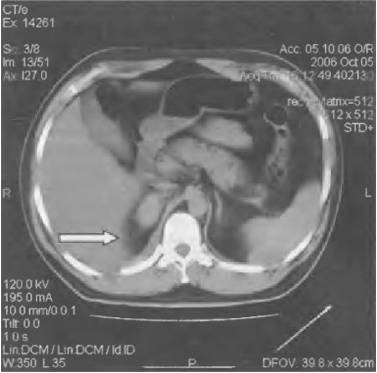

- КТ;

- компьютерной томографии;

- КТ и МРТ;

Диагностировать заболевание можно при помощи анализа крови, УЗИ почек, экскреторной урографии, КТ и МРТ.